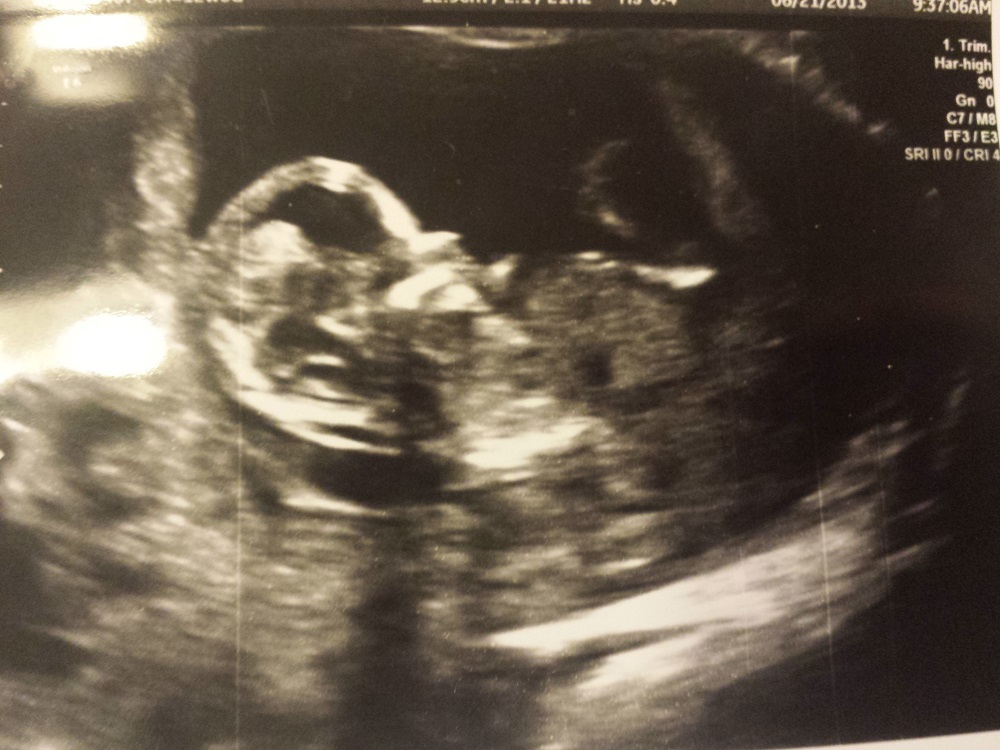

Can anyone tell if the white area down near the genitals is a nub or umbilical cord or something else? If it is a nub does it look girl or boy? Thanks!!!

looks to high up to be nub sorry . congratz tho! x